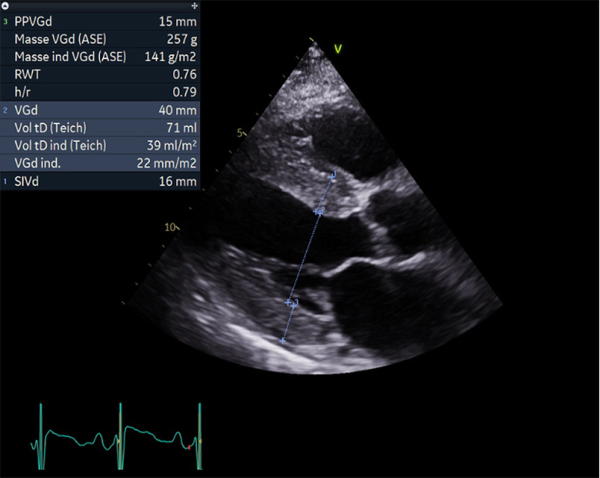

Figure 4

FEVG 40% en Simpson biplan, 45-50% visuellement. GLS -7%. Hypokinésie des bases et hyperkinésie de l'apex. VG non dilaté (DTDVG = 35mm, VTDVG =54ml/m2), hypertrophié (SIV = 18.5mm, PPVG = 19mm).

- DC = 3l/min, IC = 1.6l/min/m2 avec CCVG = 21mm et ITV sous Ao = 8cm

- OG dilatée à 40mL/m² (21cm2). OD dilatée à 19cm2

- Valve aortique tricommissurale, fine, pas de sténose ou fuite. Valve mitrale épaissie, pas sténose ou fuite

- Profil mitral restrictif, pressions de remplissage VG élevées (E/A =2.6, E/e’ moy = 22)

- Cavités droites non dilatées (Anneau tric =35mm)

- Fonction VD altérée (TAPSE = 7.7mm, S tric = 5.9cm/s)

- PAPS estimée sur IT modérée à 30 + 15mmHg (TAP 82ms)

- VCI dilatée ( 22mm), non compliante

- Lame péricardique minime